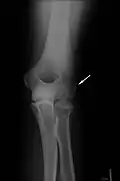

-

Klassische Zuggurtung einer Patellafraktur -

Erweiterte Zuggurtung einer Patellafraktur (mit K-Drähten) -